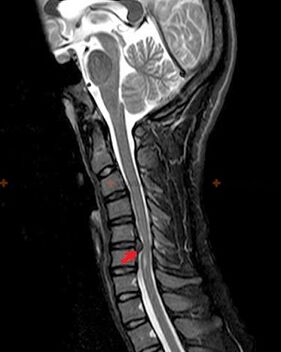

Diagnostiek en röntgensignalen

Osteochondrose is een röntgendiagnose, omdat een gedetailleerd ziektebeeld alleen beschikbaar is op het moment van exacerbatie, terwijl veranderingen in de wervelkolom kunnen optreden bij volledig subjectief welzijn van een persoon. Zonder röntgenonderzoek kunnen we alleen praten over vermoedelijke osteochondrose, omdat soortgelijke symptomen kunnen worden veroorzaakt door andere ziekten (myositis, wervelneoplasmata en andere).

Om osteochondrose te diagnosticeren worden de volgende onderzoeksmethoden gebruikt: radiografie (bij voorkeur met functionele tests), MSCT en MRI. Dit laatste onderzoek heeft de meeste voorkeur vanwege het feit dat het ons in staat stelt de toestand van de tussenwervelstructuren heel duidelijk in beeld te brengen.

Röntgensignalen van osteochondrose omvatten de volgende veranderingen in de wervelkolom:

- Verminderde hoogte van de tussenwervelschijven.

- Aanwezigheid van marginale botgroei.

- Overtreding van de locatie van de wervels ten opzichte van elkaar.

- Vervormingen van wervellichamen en bogen, enz.

De aanwezigheid van de hierboven beschreven veranderingen, evenals veranderingen in de structuur van de tussenwervelschijf, gedetecteerd door MSCT en MRI, dienen als betrouwbare tekenen die de aanwezigheid van osteochondrose bevestigen.